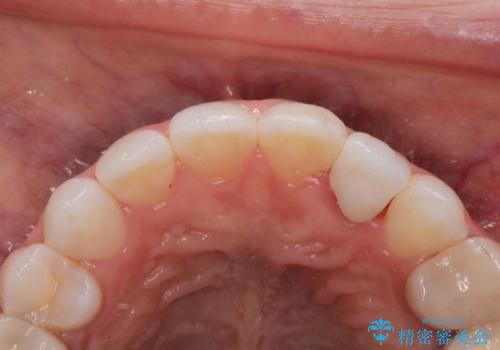

- 以前に被せ物の治療した箇所に汚れが溜まりやすいことを主訴に来院されました。

矯正治療を行なったのち、オールセラミッククラウンにて修復しております。

矯正治療はインビザラインで行なっております。